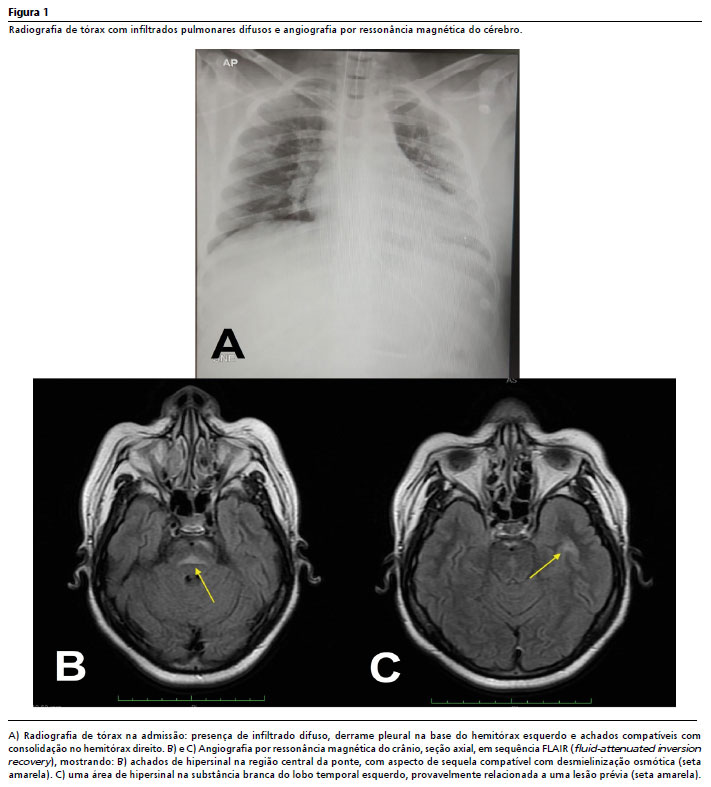

A radiografia de tórax realizada na admissão mostrou infiltrados pulmonares difusos, derrame pleural na base do hemitórax esquerdo e achados compatíveis com consolidação no hemitórax direito, sugerindo pneumonia adquirida na comunidade (Figura 1A). Foi iniciada antibioticoterapia empírica com ceftriaxona 2 g/dia (intravenoso) e azitromicina 500 mg/dia (por sonda nasoenteral), além de fenitoína 300 mg/dia (intravenoso) devido ao histórico de crises convulsivas autolimitadas não investigadas e ausência de achados indicativos de eventos agudos.

Nos dias subsequentes, foi submetida a ressonância magnética (RM) e angiorressonância magnética do encéfalo, que evidenciaram hipersinal na sequência de recuperação de inversão atenuada por fluido (FLAIR) na região central da ponte, com aspecto sequelar, possivelmente relacionado à desmielinização osmótica (Figura 1B). Também foi identificado hipersinal na substância branca do lobo temporal esquerdo, possivelmente relacionado a lesão prévia (Figura 1C).